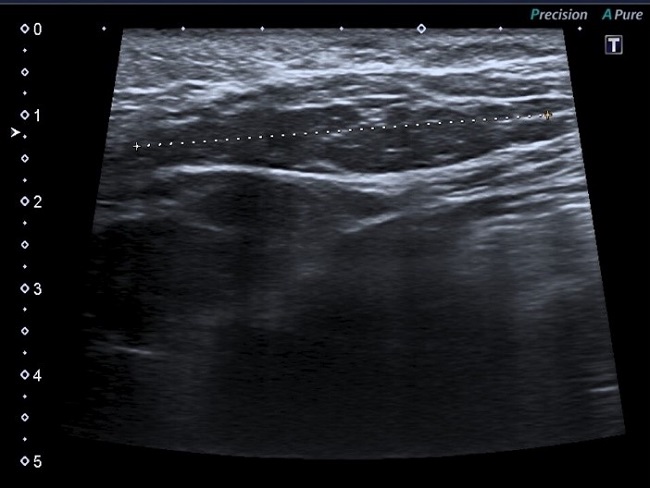

Lactante mujer de 2 meses, antecedente de arteria umbilical única y ptosis palpebral derecha, consultó por hemihipertrofia de pierna derecha y tumoración lumbar derecha. Mediante ecografía se observó un aumento del tejido celular subcutáneo de bordes imprecisos de 4 cm, con aumento progresivo a los 8 meses. A los 12 meses medía 8 x 5 x 3 cm, extendiéndose hacia el glúteo (Figura 1). Estudios cromosómico y genético normales, no encontrándose relación con ningún síndrome asociado SCAL.

En controles ecográficos posteriores presenta hipertrofia del tejido graso subcutáneo, descartando recidiva local.